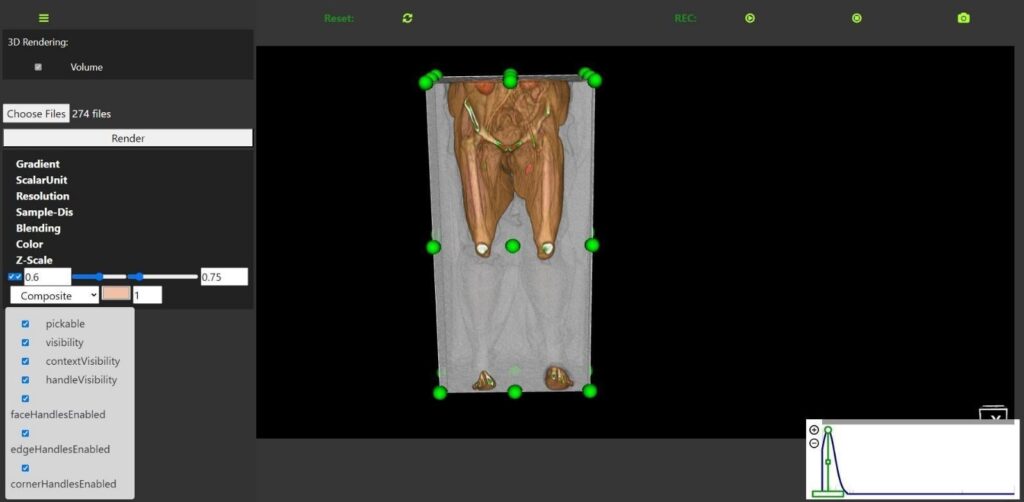

The 3D rendering module, accessible via the RESTful API endpoint/api/visualization/3d-rendering/, is a critical component of the DECODE cloud platform. This endpoint facilitates efficient data retrieval and interaction, enabling real-time updates and dynamic adjustments. Figure 7 shows the user interface for this module, highlighting its robust functionality and interactive features that significantly enhance the analysis and treatment planning

for PAD. The user interface allows users to upload and render volumetric medical imaging data seamlessly. It includes a variety of controls for manipulating 3D visualization, such as gradient adjustment, scalar unit specification, resolution settings, and sample distance control. These controls enable users to tailor the rendering process to highlight specific anatomical features, facilitating a more precise examination of the imaging data.

Interactive features such as volume clipping, rotation, zooming, and panning are integrated into the interface, allowing users to explore the 3D models from various perspectives. The presence of checkboxes for enabling or disabling visibility, context visibility, handle visibility, and various handle controls (face, edge, corner) further enhances the flexibility and customization available to the user.